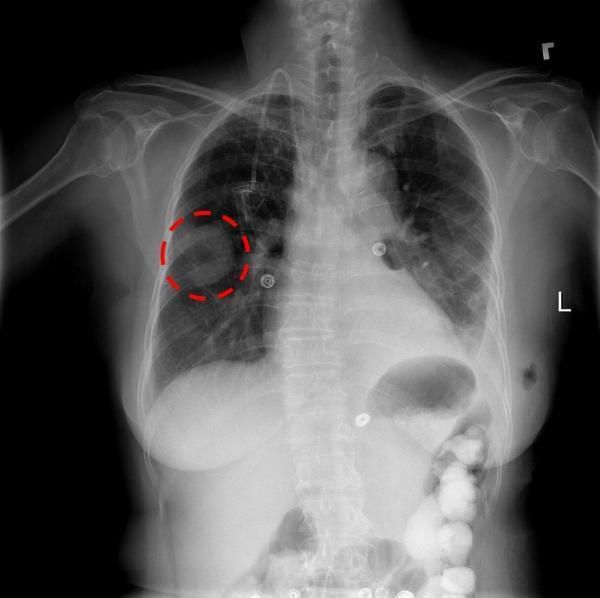

Elad Walach認為,也許人工智能能夠最快改變的醫療領域就是放射領域。人工智能將是解讀重要醫學影像的關鍵,這些醫學影像反映我們身體內部的情況,例如CT掃描、MR和X射線圖像,幫助醫生做好他們最擅長的事:診斷。

1. 放射學是可視的。醫學掃描當然是可視的,而人工智能在分析視覺圖像方面尤其強大——這至少部分歸功于人工智能技術在安全和社交媒體服務中取得的突破,它可以識別我們的面孔并從人群中找到我們。

放射領域高度依賴對視覺數據的解釋,這使得它比其他一些醫學領域更適合深度學習技術。這意味著,放射科醫師可以立即從人工智能技術的使用中受益,而精神病醫生或胃腸病專家則不能。

2. 放射科被行業急需。醫 學影像(CT和MR)的數量持續大幅度增加——它們在2016年所有檢測中分別占到了7.9%和8.9%。然而,在進行了更多掃描的同時,放射科醫師的數 量已經進入了穩定階段。而且,隨著技術的進步,每次掃描的分辨率和圖像數量呈指數級增長。因此,需要考慮的細節數量也相應地增加了。這就產生了巨大的技術 需求,這種技術可以突破日益增長的工作負荷造成的危險瓶頸——而且,正如我們所知,需要是發明之母,深度學習可以幫助評估CT和MRI掃描結果,快速找出 放射科醫師應該重點關注的區域,以便他們進一步進行檢查,同時還允許更快地評估緊急掃描——因此改善了患者的預后。

當 然,數據的挖掘也存在挑戰,挑戰在于人工智能算法如何獲取這些影像。而最近,一些醫療機構公開分享他們的匿名數據催生了這一領域的熱潮,比如,美國國家衛 生研究院(National Institutes of Health)最近公布的X射線數據集,該數據集包含了超過100,000張帶有注釋的圖像(如下圖)。